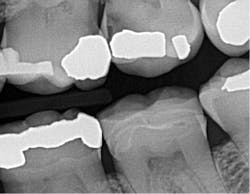

There is a direct ROI when using this sensor compared to older digital sensors or even film. I can appreciate a significant improvement in identifying interproximal and recurrent caries on patients that I thought were completely healthy. It honestly is scary what I had been missing with the previous generation of digital sensors. I also like Schick 33's presets called clinical-task-specific mapping. I can click on a preset and images automatically default to the setting I need -- general dentistry, endodontics, periodontics, or restorative dentistry. Once the image is captured, I can instantly adjust sharpness by moving my cursor left or right over the graphical slider.

The increased confidence in my interpretation of 2-D images from Schick 33 has directly affected my patients' acceptance of their treatment needs. My staff is overwhelmed by our ability to see consistently crisp and detailed digital images. With the combination of digital radiography's low-dose radiation and super crisp images, we do not hesitate to perform X-rays on all patients, and we value the diagnostic details that were once left behind.